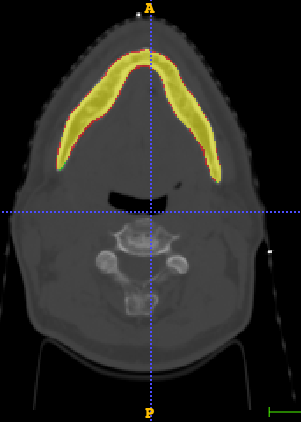

In Chapter 6, we propose an end-to-end, atlas-free 3D convolutional deep learning framework for fast and fully automated whole-volume HaN anatomy segmentation [115]. Our deep learning model, called AnatomyNet, segments OARs from head and neck CT images in an end-to-end fashion, receiving whole-volume HaN CT images as input and generating masks of all OARs of interest in one shot. AnatomyNet is built upon the popular 3D U-net architecture, but extends it in three important ways: 1) a new encoding scheme to allow auto-segmentation on whole-volume CT images instead of local patches or subsets of slices, 2) incorporating 3D squeeze-and-excitation residual blocks in encoding layers for better feature representation, and 3) a new loss function combining Dice scores and focal loss to facilitate the training of the neural model. These features are designed to address two main challenges in deep-learning-based HaN segmentation: a) segmenting small anatomies (i.e., optic chiasm and optic nerves) occupying only a few slices, and b) training with inconsistent data annotations with missing ground truth for some anatomical structures. We collect 261 HaN CT images to train AnatomyNet, and use MICCAI Head and Neck Auto Segmentation Challenge 2015 as a benchmark dataset to evaluate the performance of AnatomyNet. The objective is to segment nine anatomies: brain stem, chiasm, mandible, optic nerve left, optic nerve right, parotid gland left, parotid gland right, submandibular gland left, and submandibular gland right. Compared to previous state-of-the-art results from the MICCAI 2015 competition, AnatomyNet increases Dice similarity coefficient by 3.3% on average. AnatomyNet takes about 0.12 seconds to fully segment a head and neck CT image of dimension , significantly faster than previous methods. In addition, the model is able to process whole-volume CT images and delineate all OARs in one pass, requiring little pre- or post-processing. We demonstrate that our proposed model can improve segmentation accuracy and simplify the auto-segmentation pipeline. These contributions are released as an open-source software package called AnatomyNet, which is publicly available555https://github.com/wentaozhu/AnatomyNet-for-anatomical-segmentation. Portions of this chapter were published as part of [115].